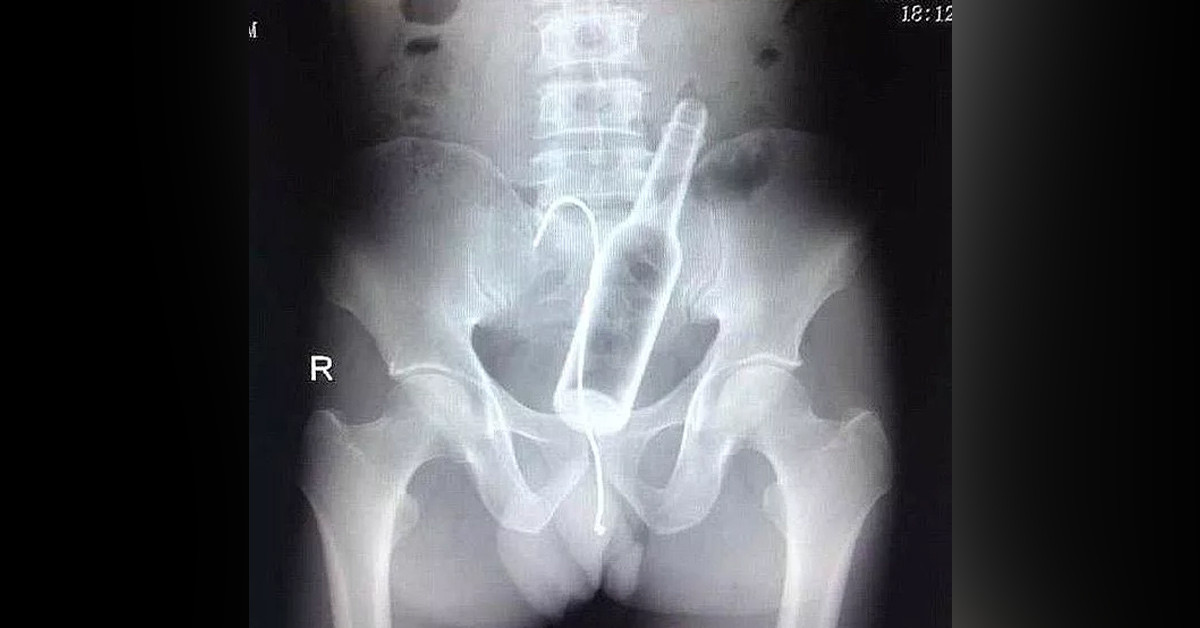

3 gün boyunca tuvalete çıkamama şikayetiyle soluğu hastanede alan adamın makatında 12 cm boyutunda bir pet şişe tespit edildi. Adamın yaptığı açıklama akıllara durgunluk getirdi.

İsmi belirtilmeyen 50 yaşında bir adam 3 gün boyunca tuvalete çıkamamasından sonra eşiyle birlikte hastaneye gitti. Adamı muayene etmeye başlayan doktorlar, muayene esnasında bir sorun göremedi. Adamın başka bir şikayeti olmadığı için röntgen filmi istedi. Röntgen filmi çekildikten sonra gerçek ortaya çıktı.